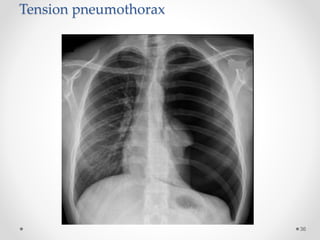

Tension

pneumothorax

Lung collapse

Mediastinal

shift

Low flat

diaphragm

Tension pneumothorax

• It is life threatening condition.

• The pleural pressure is more than the atmospheric

pressure.

Radiological manifestations of large pneumothorax

• Mediastinal shift,

• Flattening of the hemidiaphragm &

• Lung collapse.